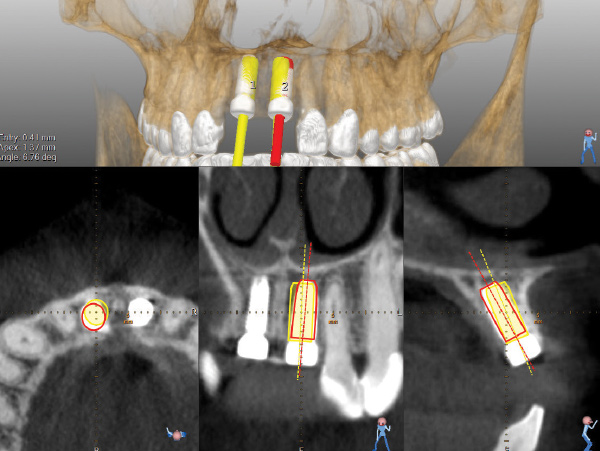

A post-placement CBCT scan was secured and compared to the preoperative CBCT plan using software inherent to the dynamic navigation system (Figure 11). Accuracy results from this case (preoperative plan compared to post-implant placement) were as follows: entry point deviation was 0.13 mm for tooth position No. 8 and 0.41 mm for No. 9; angle discrepancy was 4.3 degrees for No. 8 and 6.76 degrees for No. 9; implant apex depth deviation was 1.10 mm for No. 8 and 1.37 mm for No. 9.

In the present case report, where the surgery was performed while the authors were still in a learning curve with dynamic navigation, the entry point deviations for tooth position Nos. 8 and 9 were 0.13 mm and 0.41 mm, respectively, and the respective angle discrepancies were 4.3 and 6.76 degrees. Block et al has demonstrated that dynamic navigation has the potential to further improve accuracy measurements compared to static guides but that, on average, the clinician must perform at least 20 cases using the technology before the learning curve is mastered.27 This is encouraging considering that other medical disciplines have reported a proficiency curve ranging from 60 to 500 cases depending on the surgical subspecialty.27,28 Like the introduction of guided surgery in 2002, accuracy and outcome success are largely proportional to planning and experience.

Fig 11. Pre- and post-placement CBCT scan matched with DICOM data and accuracy evaluation for site No. 8. Yellow outlines of implant represent the planned implant position, while red outlines show the actual implant position outcome.

Figure 11